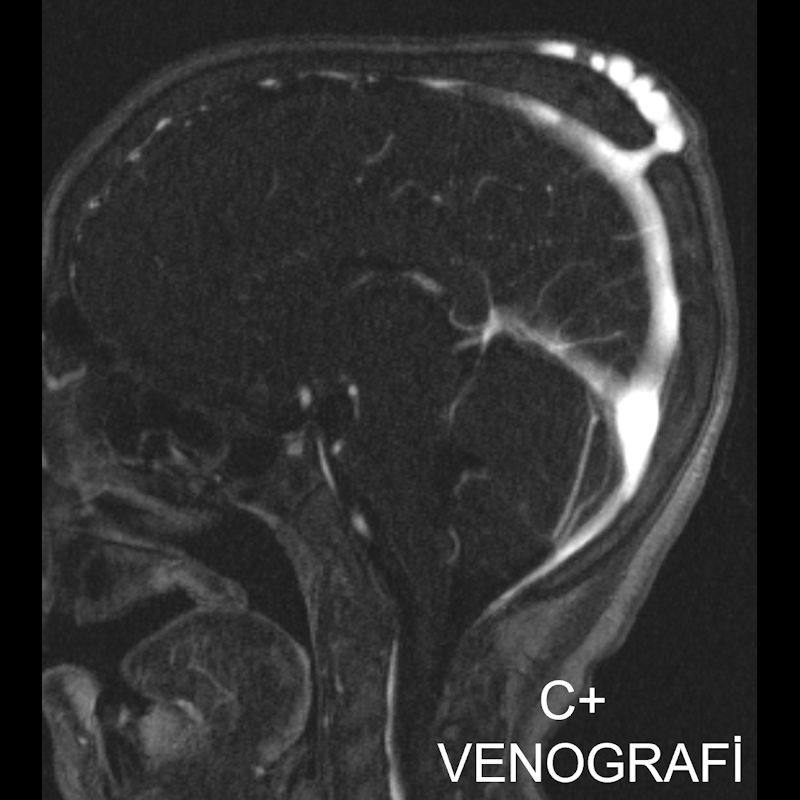

1. A) Kontrastlı FLAIR aksiyel görüntüde ve sagital T2A görüntüde vertekste orta hatta cilt altında dilate tortiyoze vasküler kollateraller (oklar). Paryetal kemikte orta hatta defekt (ok) ve defekt ile ilişkili vasküler yapıların cilt altı yumuşak dokulara uzanımı izlenmektedir.

2. B) Kontrastlı MR venografide orta hatta cilt altı dilate (oklar), tortiyoze emisserian vaskuler yapıların superior sagital sinus ile ilişkisi ve devamlılığı (ok) izlenmektedir.